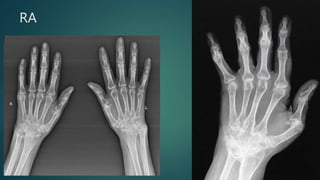

RA

 MRI is particularly sensitive to the early and subtle features of RA.

 Commonly used sequences include T1-weighted contrast-enhanced spin-echo with fat saturation and T2-weighted spin-echo or

gradient-echo sequences 2.

 Features of RA best demonstrated with MRI include 2:

• synovial hyperaemia: an indication of acute inflammation

• synovial hyperplasia (rice bodies)

• pannus formation

• decreased thickness of cartilage

• subchondral cysts and erosions:

• MRI is much more sensitive than radiography

• it is thought that subchondral cysts in RA eventually progress to erosions (i.e. constitute "pre-erosions")

• contrast enhancement may distinguish erosions or pre-erosions from degenerative subchondral cysts

• juxta-articular bone marrow oedema

• joint effusions

• #82 Almost total loss of radiocarpal, carpometacarpal and intercarpal joint spaces associated with multiple radial and carpal bone small subchondral cysts and bony fusion of trapezium, trapezoid and scaphoid bones. Diagnosis: Advanced rheumatoid arthriti

• #83 Erosive changes of intercarpal, carpometacarpal anX-ray (both hands) findings: Loss of intercarpal, carpometacarpal and distal radio-ulnar joint spaces ulnar deviation of MCP joints extension deformity of DIPs (Boutonierre deformity) and hitchhiker thumb deformit d metacarpophalangeal of the 2nd finger of right hand. Left elbow and left knee are affected as well.